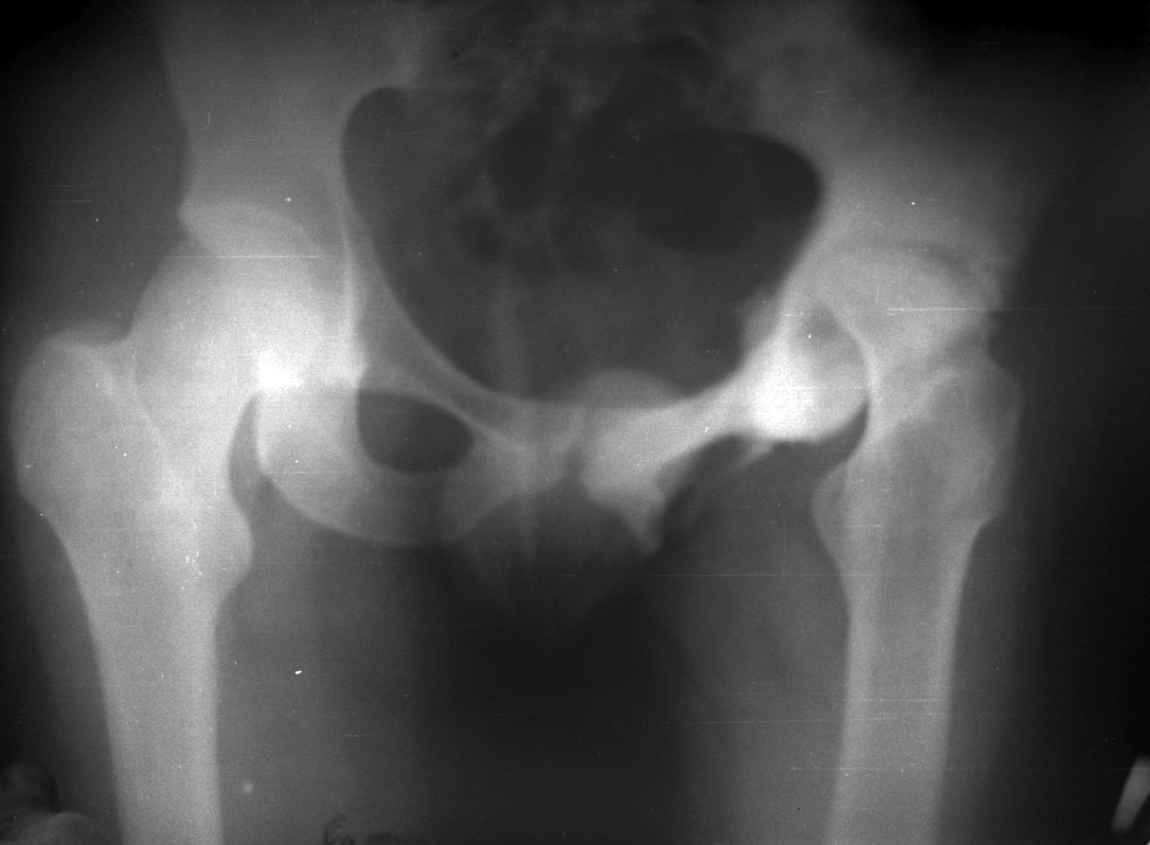

.........наверное не повезло. Но иногда это выход и очень хороший. М., 21 года спрыгнул в Армии с машины с исходом в гнойный коксит, свищевой формой в течении 1,5 лет. Операция проведена в 1988 году. результат хороший и сейчас и мы с пациентом хорошие приятели (Рентг-гр и фото прилагаю).

Еще один раз произведена реконструкция проксимального отдела юноше 17 лет с посл гематог остеомиелита тотальным дефектом проксимального отдела бедра и укорочением 16 см.(проксим отдел в виде "сосульки"). Произведена одноэтапная последовательная реконструкция, удлинение в с/з, затем в н/з. Рентгенограммы к сожалению утеряны.

Результат, поверьте, фантастический. Колено почти не пострадало. Сейчас сам удивляюсь, как хорошо получилось. РПО по Илизарову - Выход из ситуации иногда единственный, и хороший почти всегда, но трудоемкий для врача и тяжелый - пролонгированно для больного(в этом то и "собака порыта").